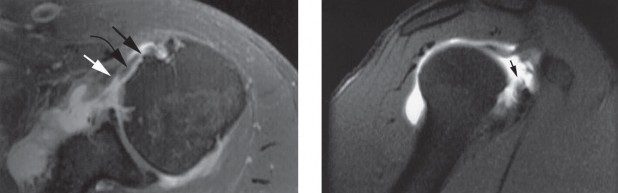

Which of the following findings is indicative of a subscapularis tendon tear?

The answer is (B). As the four layers of the lateral rotator interval insert onto the lesser tuberosity of the humerus, they form the “reflection pulley” that forms a sling around the tendon of the long head of the biceps before it enters the bicipital (intertubercular) groove. A tear of the upper part of the subscapularis can disrupt this reflection pulley and destabilize the biceps tendon, allowing it to sublux or even

dislocate out of its groove, usually in a medial direction. If this happens, the intertubercular groove will be empty on MRI. Often, a “pulley sign” will also be seen on MRI when this occurs. This is when contrast material extravasates extra-articularly just over the superior border of the subscapularis tendon on axial images (see Fig. 2–11).

Figure 2–11_Axial T1 MRI. Left: an empty intertubercular sulcus, positive pulley sign (straight _black arrow on left), and dislocated biceps tendon (curved black arrow). Right: fraying subscapularis tendon (arrow). (From Lyons RP, Green A. Subscapularis tendon tears. J Am Acad Orthop Surg. 2005;13(5):353–363.)